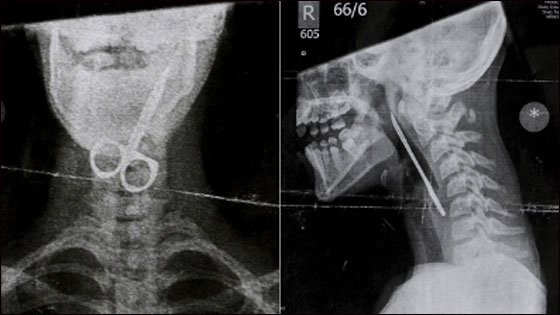

ووضع كيرتيس فرانسيس، 12 عاما، مقص الأظافر في فمه لينزلق سريعا في حنجرته وبدأ يسعل دما. وبعد أن نقل على عجل إلى أقرب مستشفى، أوضحت صور الأشعة السينية وجود المقص داخل الحلق دون أن يشعر الفتى بأي صعوبة في التنفس رغم أنه كان يبدو عليه التعب والإرهاق. ونجح الأطباء، الذين أصابتهم الدهشة، في إزالة المقص خلال عملية جراحية استغرقت 90 دقيقة تحت التخدير العام.